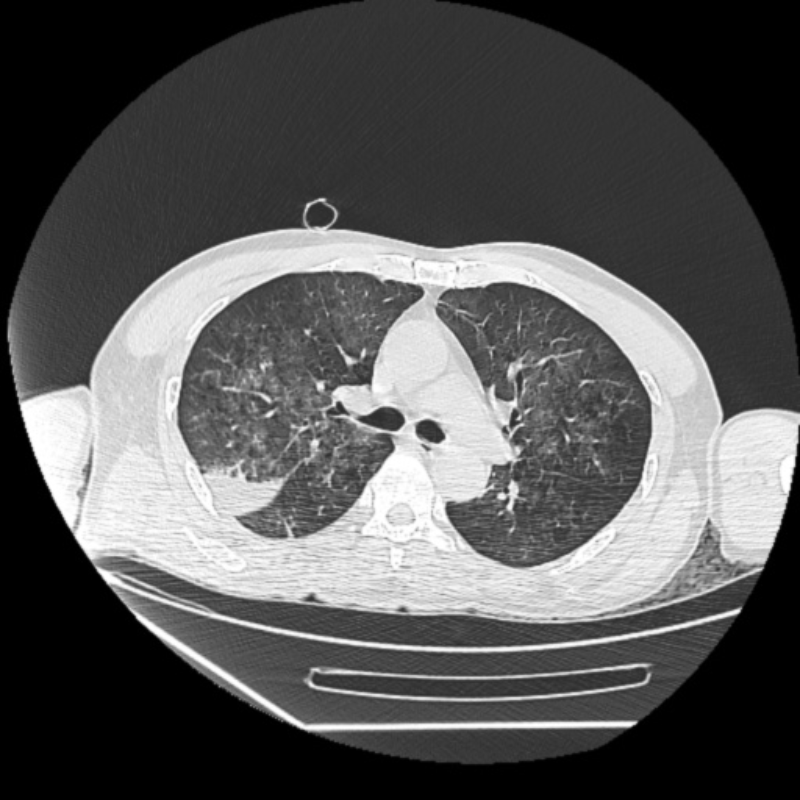

容伯伯入住重癥醫(yī)學科后,值班醫(yī)生周明醫(yī)師給予雙肺纖維支氣管鏡檢查,鏡下所見氣道內(nèi)可見渾濁的液體,考慮患者在魚塘中溺水所致,周明仔細操作,反復灌洗,不斷吸引,把容伯伯雙肺的臟水污物清除干凈。重癥醫(yī)學科陳勁飛主任查看容伯伯病情,考慮魚塘中病原微生物條件復雜,指示抗感染予廣覆蓋常見的革蘭氏陰性菌、陽性菌、真菌等,同時患者心肺復蘇后,予加強低溫腦保護,機械通氣、化痰、加強其他臟器功能保護、營養(yǎng)支持等綜合治療……

經(jīng)重癥醫(yī)學科醫(yī)護團隊積極精準治療后,容伯伯逐漸清醒過來,當他張開雙眼看到親人的那一刻,非常激動。兩天后,容伯伯呼吸道癥狀改善,成功脫機呼吸機,待病情平穩(wěn)后轉(zhuǎn)至呼吸與危重癥醫(yī)學科繼續(xù)治療,目前已痊愈出院,恢復良好。